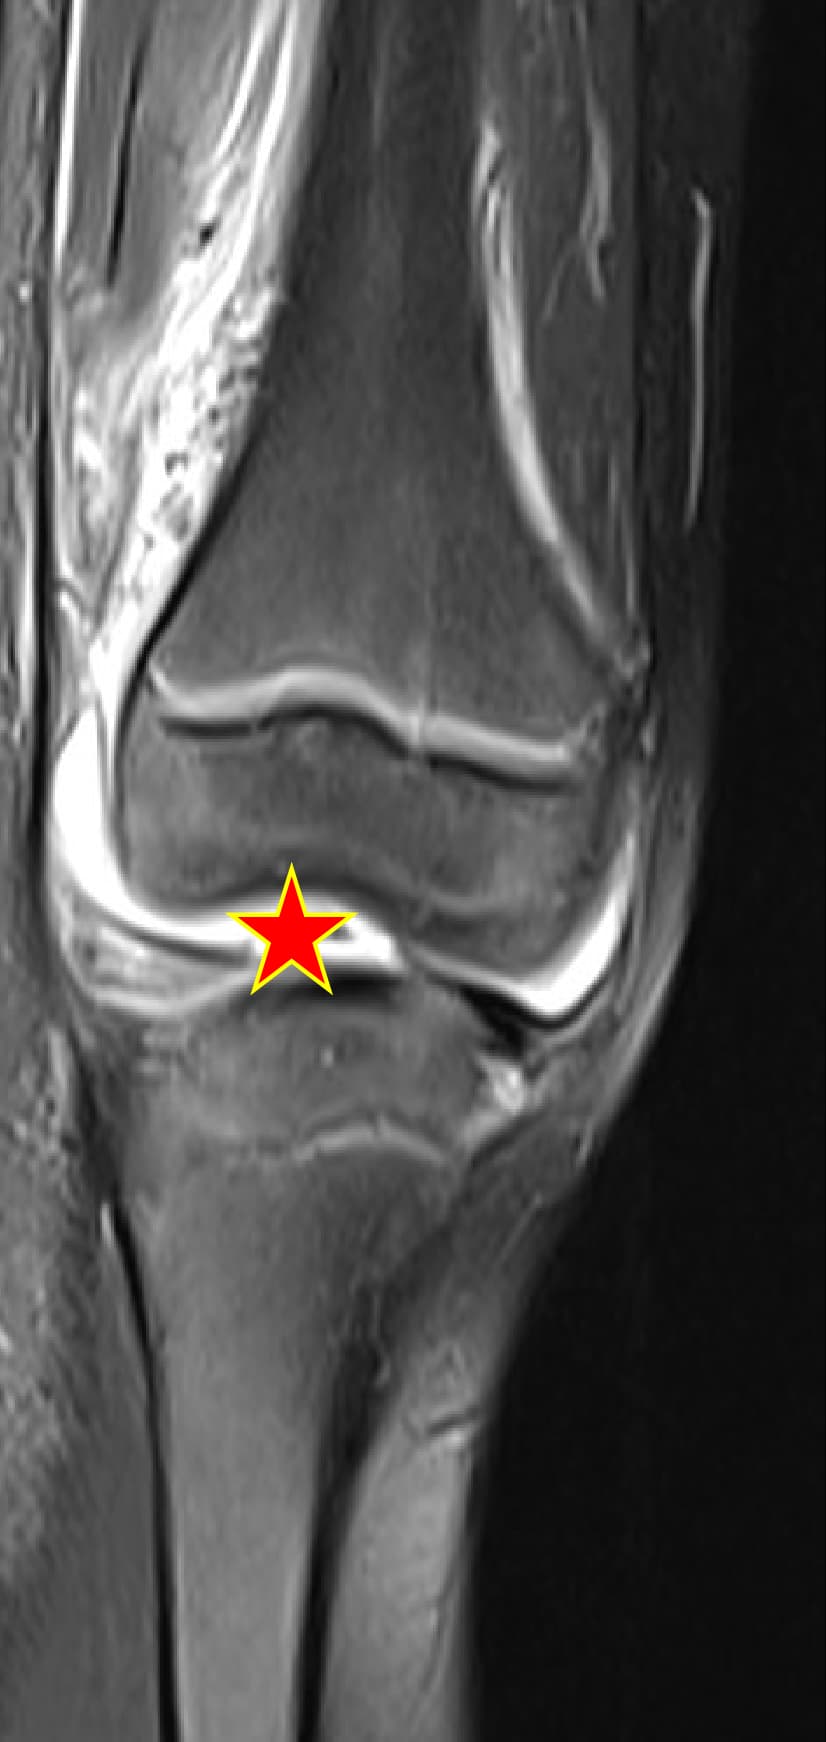

Hip & knee arthritisMRI case galleryClinical insights

Septic arthritis cases